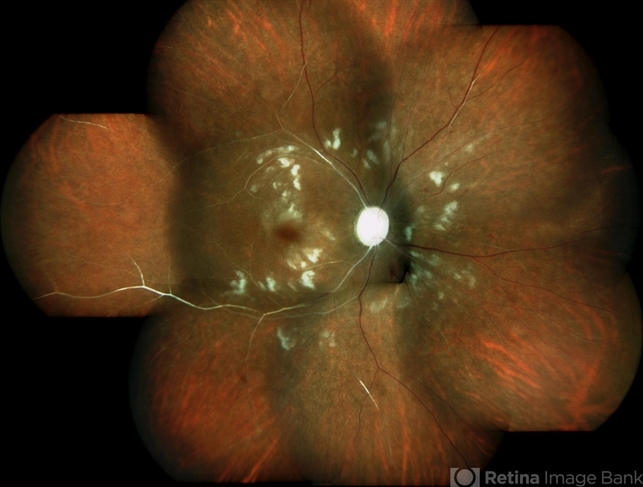

- systemic lupus erythematosus (SLE) vasculitis, systemic lupus erythematosus (SLE) retinopathy

- Colour fundus montage image of a 33-year-old young lady with history of Systemic Lupus Erythematosus of 6 years showing classic SLE retinopathy with multiple cotton wool spots , few haemorrhages and multiple small vessel sheathing s/o SLE vasculitis.